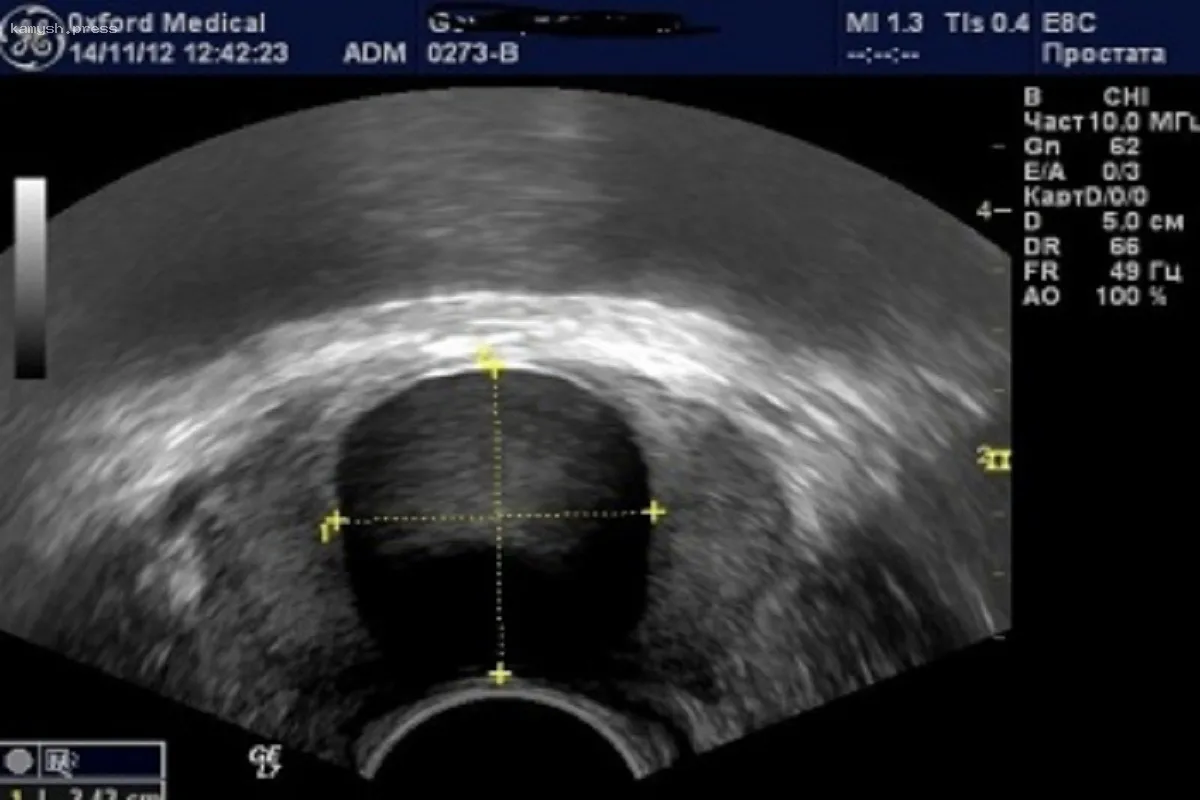

В Новосибирской области наблюдается рост случаев диагностики рака простаты. В структуре онкологических заболеваний данная форма рака занимает третье место.

По данным Новосибирского областного онкодиспансера, у 73,5% пациентов болезнь была обнаружена на ранней стадии. В общей сложности рак простаты диагностирован у 1405 человек в регионе.